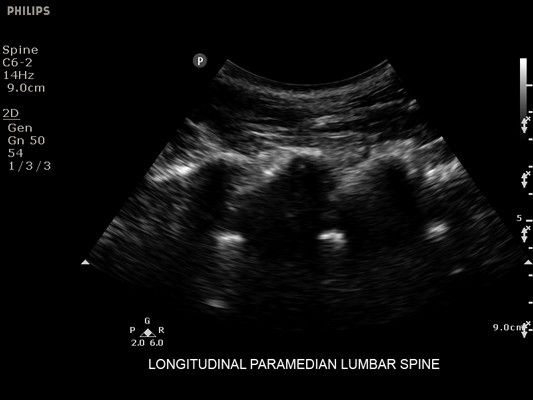

УЗИ-аппарат

Philips Sparq

Ультразвуковая система Philips Sparq упрощает процесс сканирования и интерпретацию ультразвуковых изображений в ОРИТ, позволяя врачу уделять больше внимания пациентам.

Philips Sparq - это инновационная ультразвуковая система, разработанная специально для работы в отделениях реанимации и интенсивной терапии. Система позволяет врачам сконцентрироваться на пациенте, автоматизируя рутинные процессы настройки и упрощая процедуру сканирования.

• Метки центральной линии на датчиках L12-4 и C6-2 для упрощения внеплоскостной навигации

• Конвексный УЗИ датчик Philips С6-2